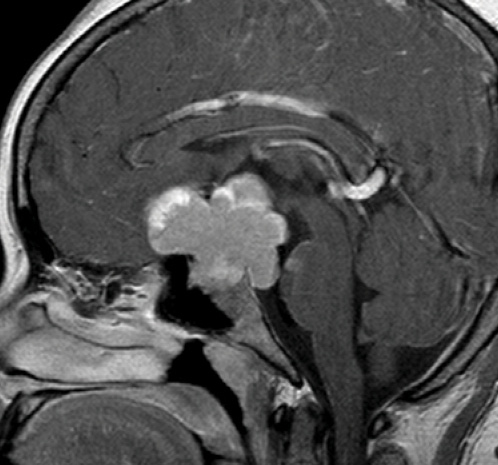

Figure 2. Magnetic resonance imaging of the same patient shows a large mass impinging on the chiasm.

The glaucoma examination is more challenging than a routine eye examination. The former requires a detailed evaluation of both the posterior and anterior segments, including the angle. I look for clues to secondary glaucomas that someone else may have missed or for evidence of retinal or neurologic pathology that is mimicking glaucoma. I am sure all of my colleagues have examples of patients who were monitored elsewhere for low-tension glaucoma who actually had an intracranial tumor (Figures 1 and 2).